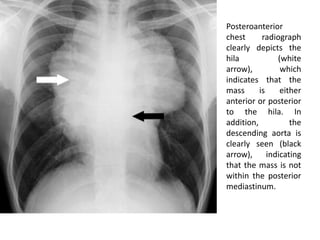

Posteroanterior

chest radiograph

clearly depicts the

hila (white

arrow), which

indicates that the

mass is either

anterior or posterior

to the hila. In

addition, the

descending aorta is

clearly seen (black

arrow), indicating

that the mass is not

within the posterior

mediastinum.